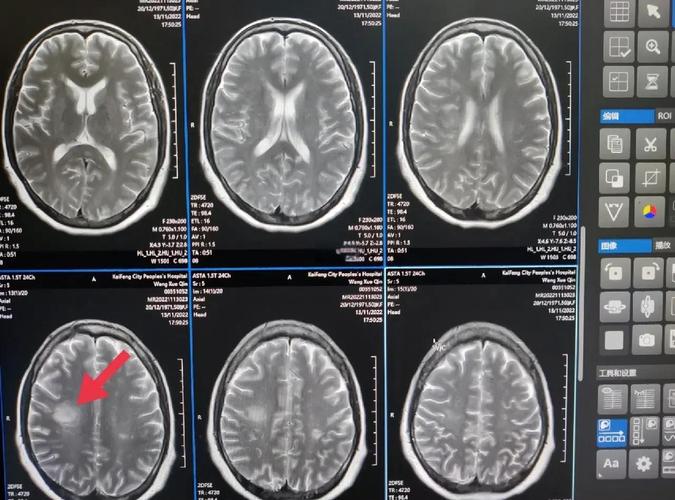

- 什么是脑梗病灶? 脑梗,全称“脑梗死”或“缺血性脑卒中”,是指因为脑部血管堵塞,导致局部脑组织缺血、缺氧而发生的坏死,这个坏死区域,在影像学检查(如CT或MRI)上显示出来的“印记”,脑梗病灶”,它就像身体其他部位(如心脏)的“心梗”一样,是脑组织受损后留下的痕迹。

- “多处”意味着什么? “多处”说明这种血管堵塞事件不是第一次发生,而是可能已经发生过多次,只是之前没有症状或者症状轻微未被察觉,每一次堵塞都会留下一个病灶,这提示我们,导致血管堵塞的根本原因依然存在,并且正在持续对大脑造成损害,核心任务是找到并控制这个“根本原因”。

- 头颅MRI+DWI+MRA/CTA: MRI是发现脑梗病灶最敏感的检查,MRA(磁共振血管成像)或CTA(CT血管成像)可以查看脑血管有无狭窄或闭塞。